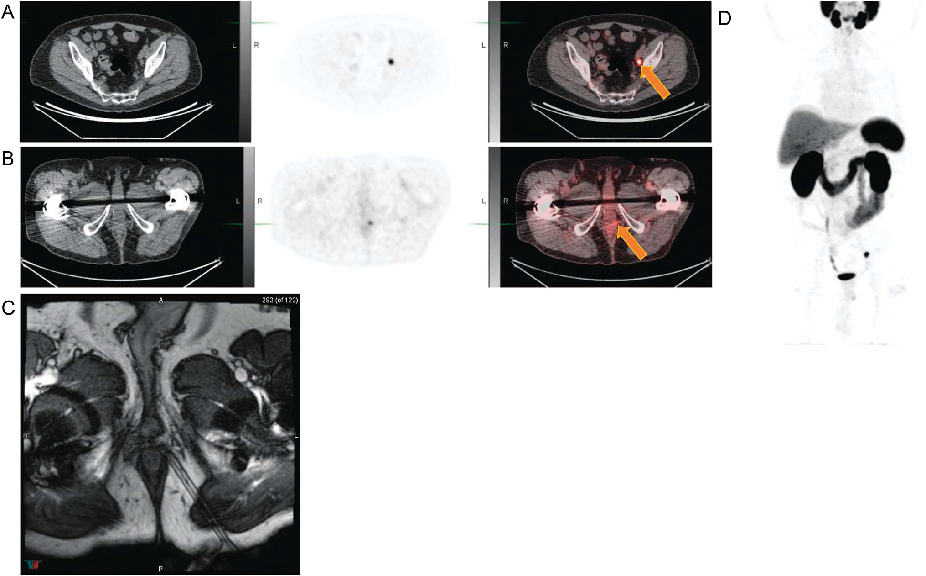

笔者认为基于flotufolastat有望实现真正意义上的PSMA靶向核素诊疗一体化,如natF-177Lu-flotufolastat +18F-natLu-flotufolastat的配合使用,二者具有完全相同的分子结构,基于18F-natLu-flotufolastat的PET-CT成像,可以实现对natF-177Lu-flotufolastat精准的治疗方案规划、治疗响应预测、治疗效果评估等。目前,flotufolastat在美国和欧洲已完成“用于生化复发前列腺癌的PET-CT诊断性能的评估与安全性研究”的多中心三期临床实验(详见下期分享)[9],部分PET结果如下图5所示,国内已有药企开始布局flotufolastat的三期临床实验,希望flotufolastat能够顺利完成临床实验,早日造福前列腺癌患者。

图5 18F-flotufolastat三期临床试验中的典型PET图像[9]